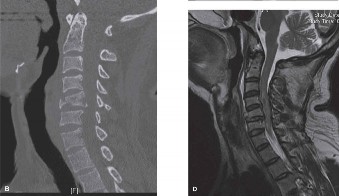

The diagnostic imaging workup for this patient spanned his initial presentation at age 15 and his subsequent return at age 20, providing a textbook illustration of the natural history of untreated isthmic spondylolysis. During his initial visit, standard weight-bearing anteroposterior (AP), lateral, and bilateral oblique radiographs of the lumbar spine were obtained. The lateral radiograph demonstrated a normal lumbar lordosis and preserved L5-S1 disc space height, with no evidence of anterior translation (spondylolisthesis). However, the oblique radiographs revealed the pathognomonic "collar on the Scotty dog" sign. The "Scotty dog" represents the posterior elements of the vertebra, where the nose is the transverse process, the eye is the pedicle, the front leg is the inferior articular process, and the neck is the pars interarticularis. A radiolucent line across the neck confirmed the presence of bilateral L5 pars defects.

Had the patient been compliant with follow-up during his initial presentation, advanced imaging such as a Single Photon Emission Computed Tomography (SPECT) scan or a Magnetic Resonance Imaging (MRI) scan with Short Tau Inversion Recovery (STIR) sequences would have been indicated. These modalities are highly sensitive for detecting acute stress reactions and marrow edema in the pars interarticularis before a frank fracture line becomes visible on plain radiographs. An MRI at that early stage would have likely shown high signal intensity in the bilateral L5 pars regions on T2-weighted STIR images, confirming an active, metabolically "hot" lesion that possessed a high potential for healing with rigid bracing.

Upon his return five years later, the imaging profile was drastically different. Standing lateral radiographs now revealed a Meyerding Grade 2 spondylolisthesis at L5-S1, indicating that the L5 vertebral body had translated anteriorly by 25% to 50% over the sacral promontory. Furthermore, there was a noticeable collapse of the L5-S1 intervertebral disc space, signifying advanced degenerative changes secondary to the altered biomechanics and chronic instability. We also meticulously measured the patient's spinopelvic parameters on a standing 36-inch scoliosis cassette. His Pelvic Incidence (PI) was measured at 65 degrees (high), which mathematically dictates a higher Sacral Slope (SS) and Pelvic Tilt (PT). A high PI is a known biomechanical risk factor for the progression of spondylolisthesis, as it creates a steeper lumbosacral shear angle, placing immense anterior translational force across the compromised L5-S1 segment.

To evaluate the neural elements and the soft tissue structures, a comprehensive MRI of the lumbar spine without contrast was obtained. The T2-weighted sagittal and axial sequences confirmed the Grade 2 anterolisthesis and demonstrated severe bilateral foraminal stenosis at L5-S1. The exiting L5 nerve roots were severely compressed between the hypertrophied, fibrocartilaginous pseudarthrosis tissue of the pars defect dorsally, and the bulging, degenerated L5-S1 disc and superior endplate of S1 ventrally. Furthermore, the MRI revealed Modic Type II changes (fatty replacement of the subchondral bone marrow) in the adjacent vertebral endplates, confirming chronic biomechanical stress and discogenic degeneration. The central canal remained relatively patent, which is characteristic of isthmic spondylolisthesis, as the posterior neural arch is left behind during the anterior translation of the vertebral body.